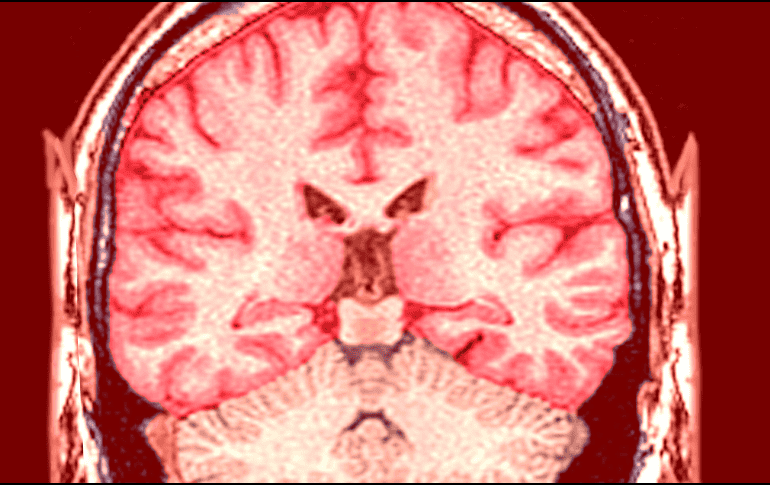

La magnitud del problema se refleja claramente en las estadísticas globales más recientes sobre salud neurológica. ESPECIAL

La magnitud del problema se refleja claramente en las estadísticas globales más recientes sobre salud neurológica. Tan solo en el año 2021, se reportaron cerca de 11.9 millones de nuevos casos de infartos cerebrales a nivel mundial.